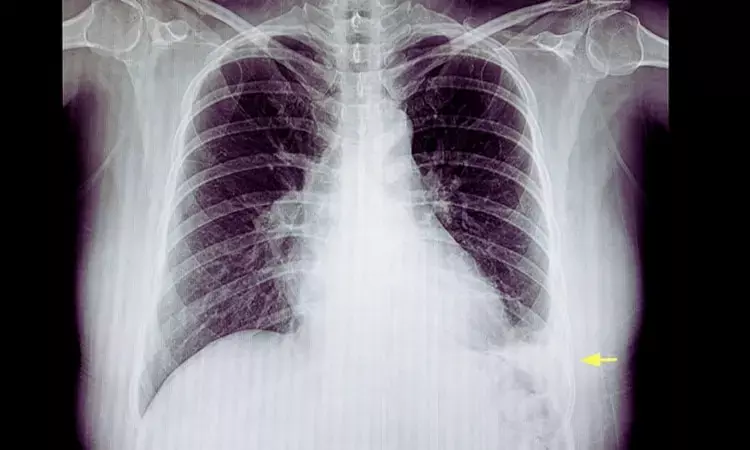

Intrapleural Enzyme Therapy Outperforms Saline Lavage in Pleural Infection: SCOPE Trial

Spain: A study published in the European Respiratory Journal reports that saline lavage alone may prolong pleural drainage in patients with pleural Infection compared with intrapleural enzyme therapy (IET). The findings also indicate that adding saline lavage to IET does not provide a meaningful clinical advantage over enzyme therapy alone.

- Early radiographic improvement was similar across all treatment groups.

- By day 2, all groups showed a median reduction of about 30% in pleural effusion size.

- By day 5, patients receiving enzyme therapy demonstrated greater pleural fluid resolution, with a median residual effusion of zero.